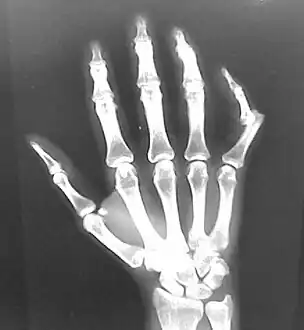

- Finger: Interphalangeal (IP) or metacarpophalangeal (MCP) joint dislocations[31]

Dislocation of the carpo-metacarpal joint.